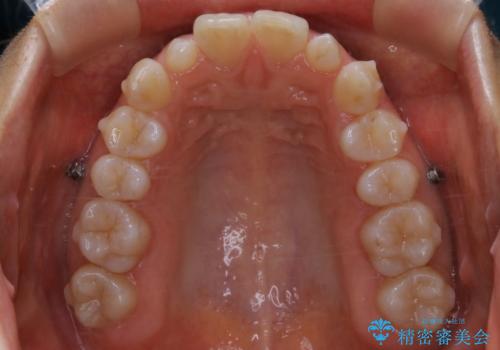

- 上の前歯が大きい事と下の前歯のがたつきを気にされてご相談にいらした方です。上の2番目の歯が矮小歯であったため、矯正治療にて歯のスペースを作った後、矮小歯には被せ物をして前歯のバランスを整えました。

歯科技工士さんとの打ち合わせを重ね、周囲の歯としっかりなじむ天然歯のような被せ物をお作りすることが出来ました。

矯正治療と補綴治療をうまく組み合わせることで、美しい口元に仕上げることが出来ました。矯正治療、補綴治療をまとめて行える総合歯科治療を体現した治療といえます。